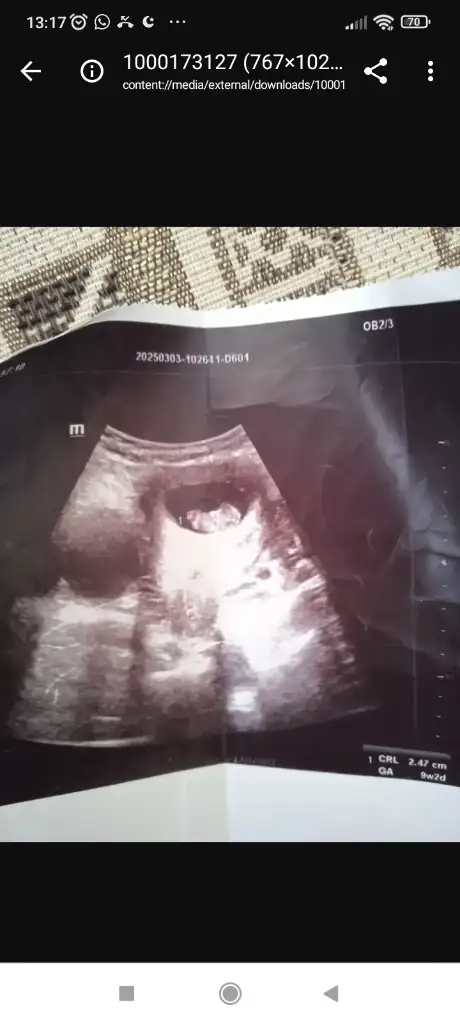

Hülya hanım 8 haftalık görüntü karından yorumlar mısınız lütfen6-7-8 haftalik baska usg var mi

Merhaba 8 haftalık karından yorumlar musun lütfenMerhaba Allah kucağınıza almayı nasip etsinerkek bence

Merhaba rica edersem bana da bir tahminde bulunabilir misiniz 8+4 günlük karından ultrasonMerhaba kız olabilir